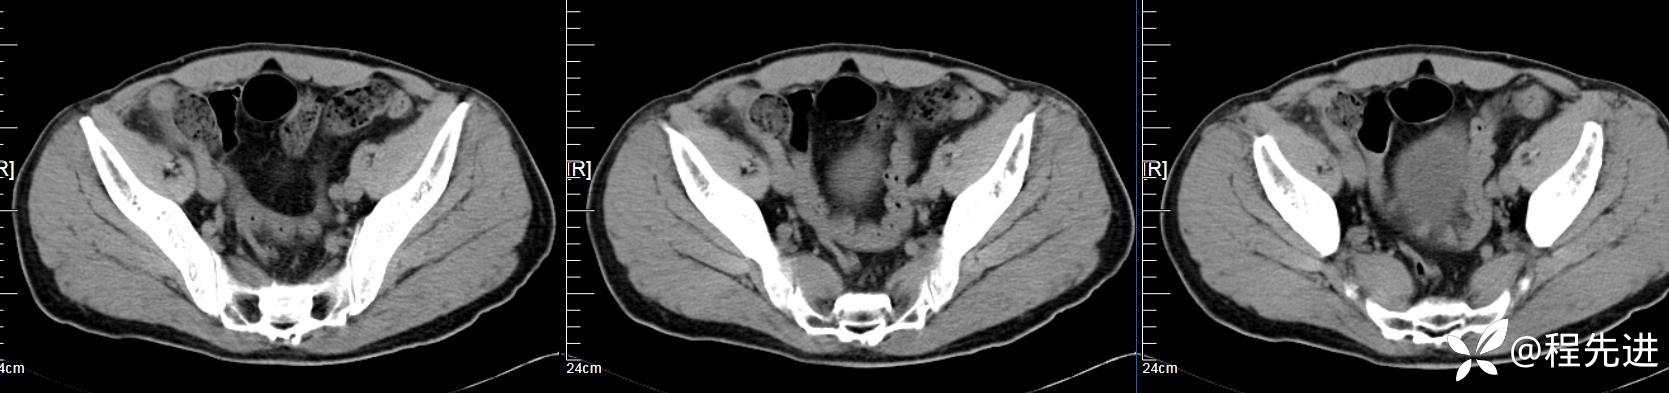

【患者信息】:男,61岁

【现病史及既往史】:右下腹部疼痛伴腹胀2天

【影像检查】